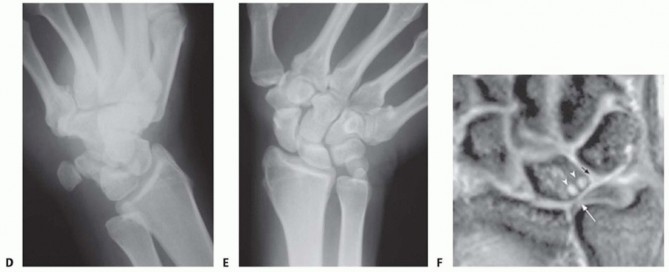

Make an 8- to 10-cm incision over the subcutaneous border of the ulna as previously described (TECH FIG 1A).Elevate the ECU muscle-tendon from the distal dorsal aspect of the ulna to allow sufficient room for a six-or seven-hole AO dynamic compression plate (Synthes LC-DCP, Synthes, Paoli, PA) (TECH FIG 1B).Take care to avoid disrupting the ECU subsheath distally.

TECH FIG 1 • A. An 8- to 10-cm incision over the subcutaneous border of the ulna. B. Six-hole AO-type dynamic compression plate (DCP) (Synthes). Avoid interfering with the osteotomy when placing the pins by referring to the line drawn at the proposed osteotomy site.Place the pins palmar enough to allow the plate to be securely seated over the dorsal surface of the ulna.